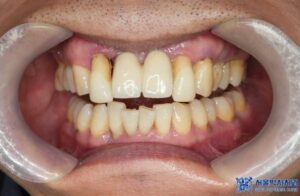

수정구치과 앞니 임플란트가 흔들려요.

보철물 제거 후 임플란트 보철 제작 사례

오늘 소개해드릴 환자분도 타 치과에서 받은

상악 앞니 임플란트가 너무

흔들린다며 내원하셨습니다.

환자분의 기존 보철물과 지대주를 제거하고

보철물 제작을 위한 스캔을 진행하였습니다.